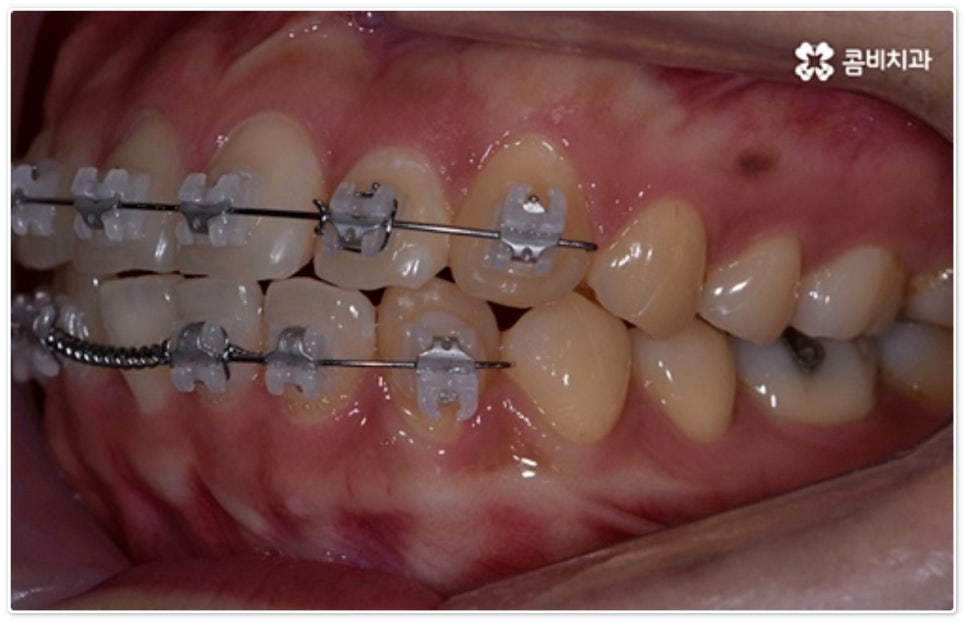

그렇지 않고 전후방 각도 조절 또는 단순 횡적인 움직임으로 치열 개선이 가능한 케이스는 부분 교정을 진행하는데, 사진에서 보시는 사례가 바로 그런 경우에 속하고 있습니다. 앞니 6개에만 브라켓을 부착하였는데 보시다시피 치아 색상과 유사한 세라믹 재질의 장치를 이용하여 심미성 또한 높여 주었음을 알 수 있어요.